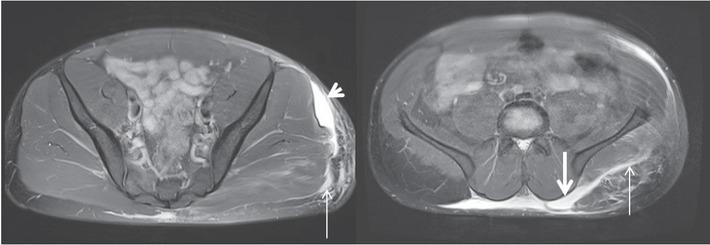

Figure 3